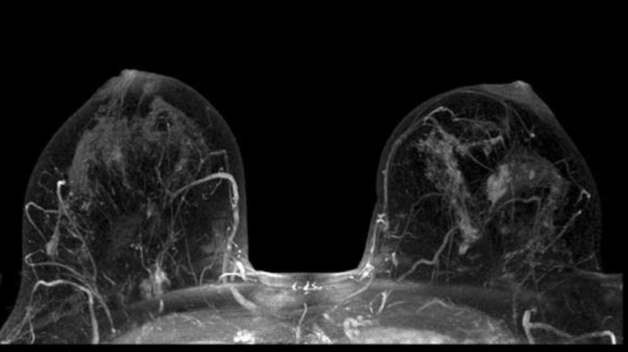

Hình ảnh tuyến vú được chụp bằng phương pháp MRI

Chụp MRI là phương pháp chẩn đoán hình ảnh hiện đại với nhiều ưu điểm vượt trội trong việc tầm soát ung thư vú